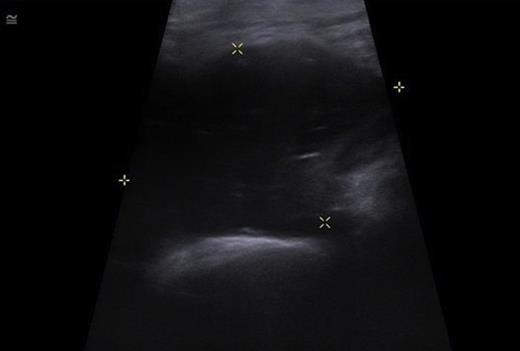

The patient underwent a Doppler scan which ruled out a DVT, then a CT scan of the left hip and thigh (figure 2). This demonstrated generalised superficial oedema with a small collection over the lateral thigh, and an irregular low density appearance of the gluteus and psoas muscles. With progressive deterioration in clinical state, the patient underwent ultrasound scanning of the thigh and hip. This demonstrated a small hip effusion with a large gas containing echogenic collection in the left psoas muscle (figure 3).

USS of the hip demonstrating a large echogenic collection in the left psoas containing gas.